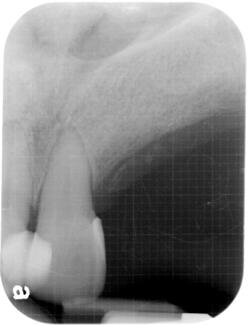

3 Implants at front:

Jan 2009

This is at front, right below the nose. In this case, there is very little room available.

3 implants are placed uneventful, right below the nasal cavity.